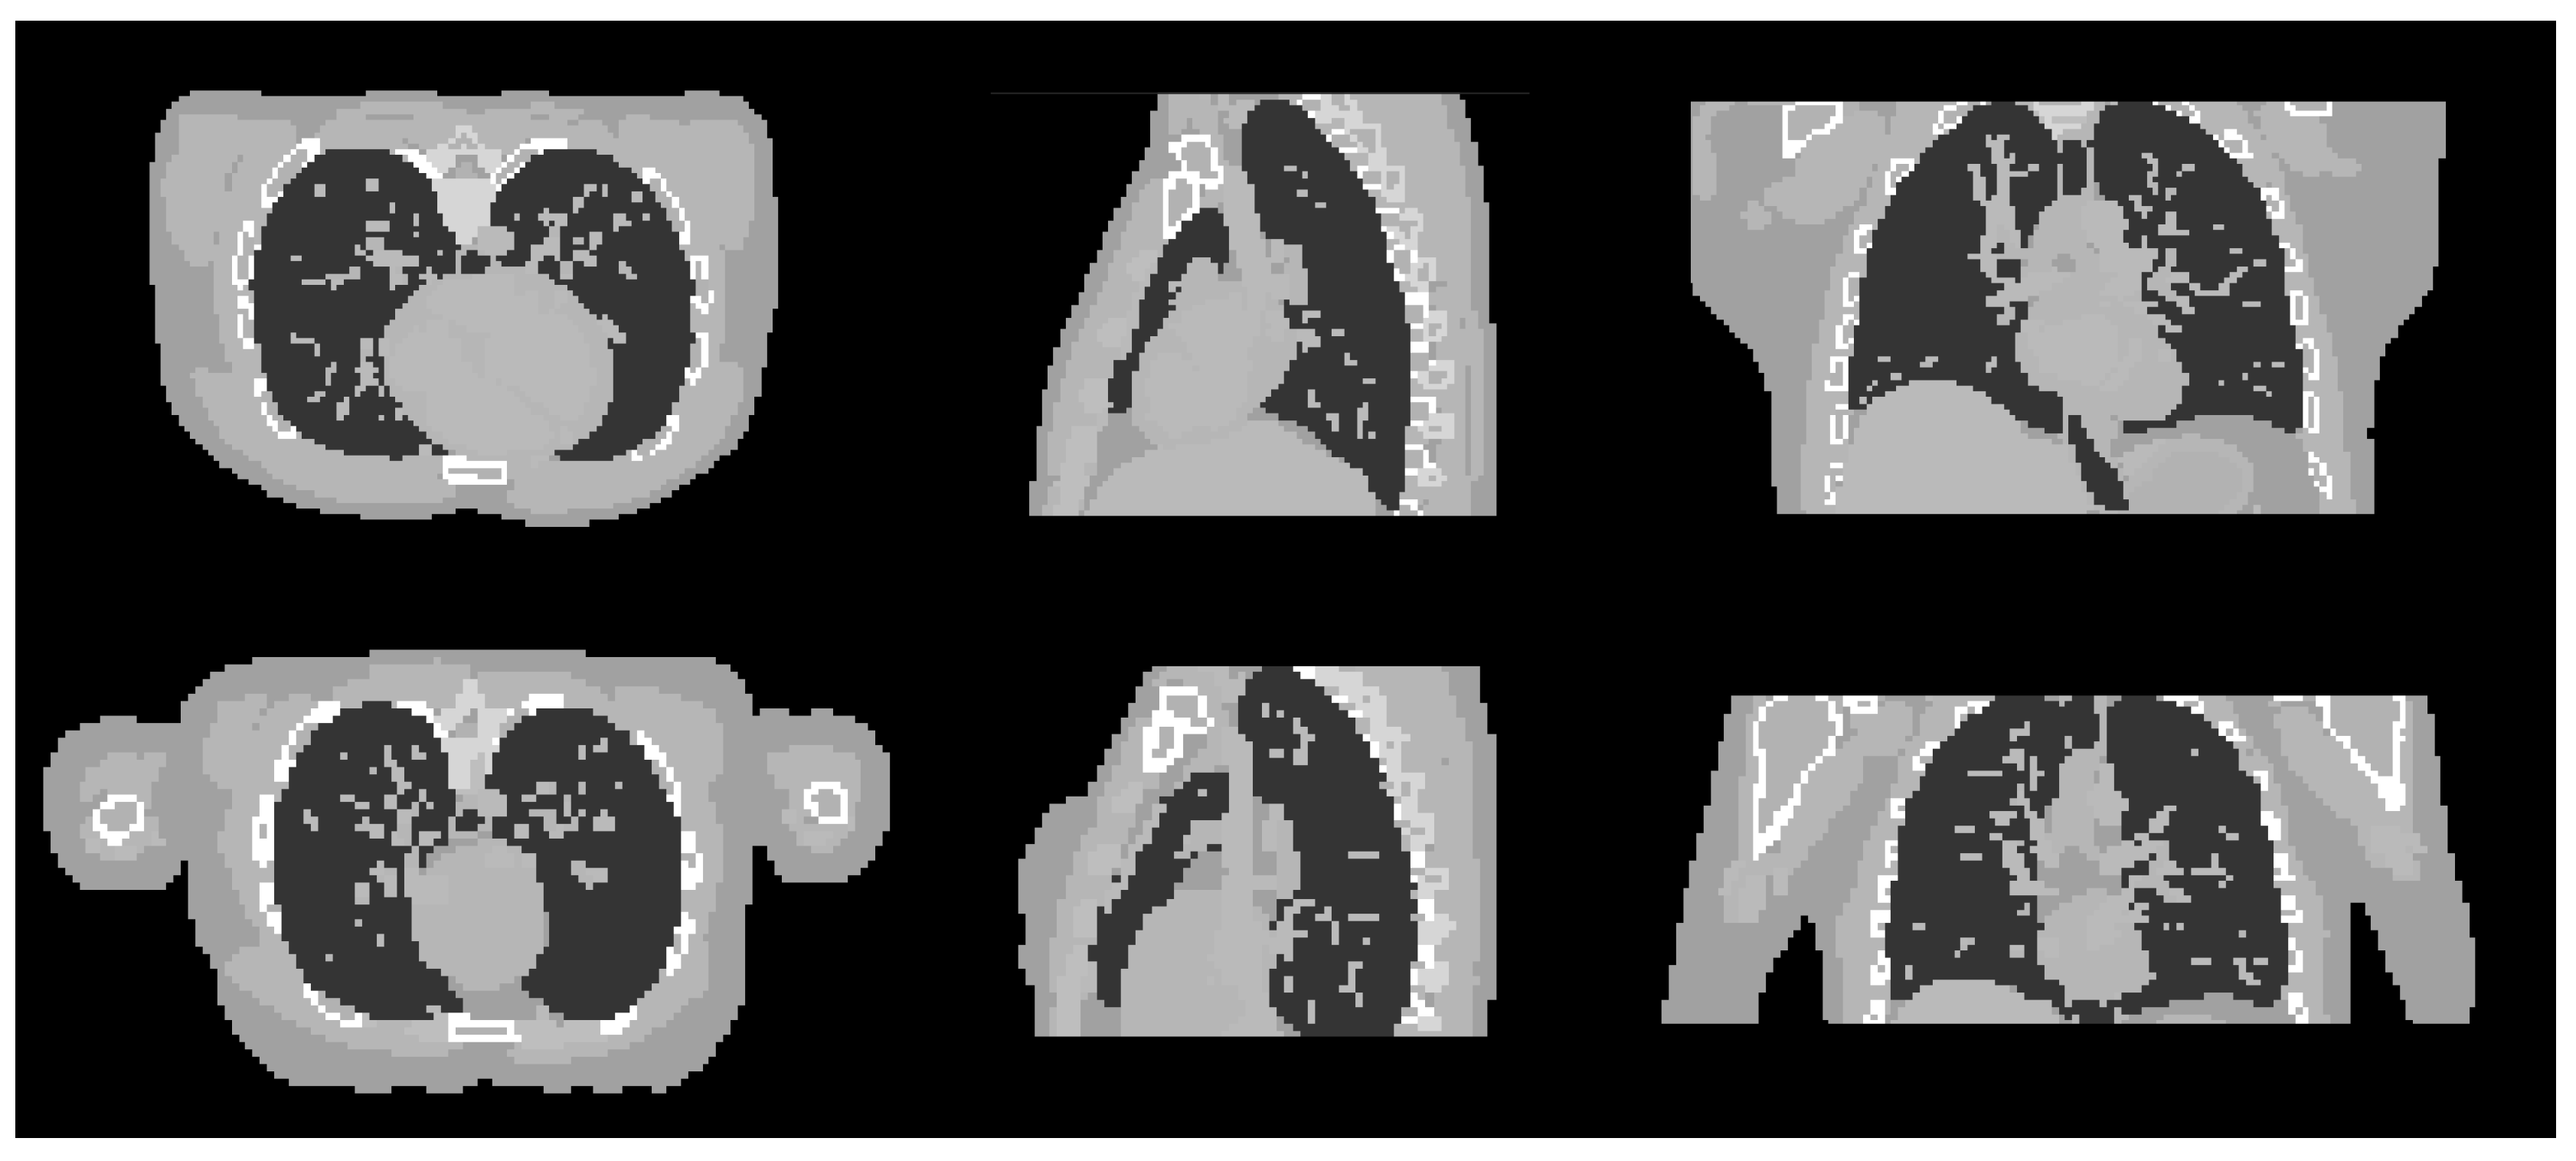

Figure 9.

Cross sectional slices of the male (top row) and female (bottom row) phantoms in the three axes.

4.3. Experiments with Different Datasets

For the next part of the study, the best set of hyper-parameters obtained from the previous experiment are applied to the reconstruction of different datasets with the same context, i.e., similar assumption about the x-ray measurements and materials/tissues. The aim is to observe whether the best hyper-parameters from the implementation of the proposed Hedge-based approach using one set of data can be readily applied to different datasets. For this purpose, we produced two new imaging data using also the digital XCAT phantom, but with different anatomical and motion parameters as shown in Table 4. The two datasets, male and female phantoms, are generated to represent the cases of different patients with different genders, as well as anatomical structures of the bodies. The parameters were specified randomly, aiming to generate as many differences as possible between the two datasets. The projection data were generated in the same way as in the first dataset. For the male phantom, the detector size is 512 × 512 pixels, with each pixel’s size of 0.8 mm. The image size is 128 × 128 × 70 voxels with the total size of 256 × 256 × 140 mm and image voxel’s size is 2 mm. For the female phantom, the detector size is similar to that of the male phantom. The image size is 128 × 128 × 48 voxels with the total size of mm and image voxel’s size is 2 mm. The experiments with these two datasets were also conducted using 50 projection images, equally sampled over 360. Cross-sectional slices of the two phantoms are shown in Figure 9.